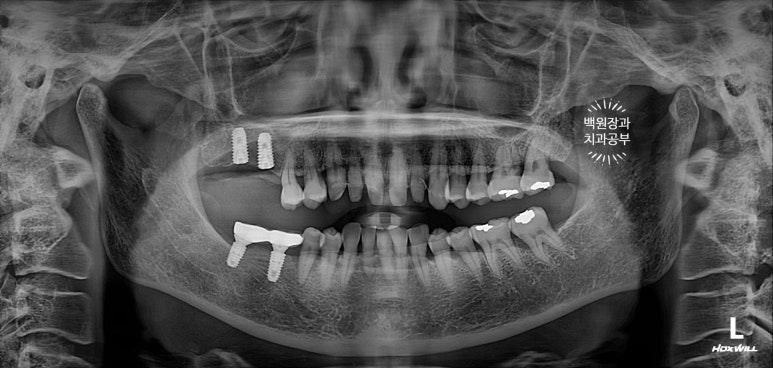

오른쪽 위 어금니 2개가 비어있어, 상악동 뼈이식술을 하면서 임플란트 2개를 심어드렸습니다.

이 것은 치주과 전문의인 제 작품입니다!! 두 명의 전문의가 상주하는 치과이지요 :)

임플란트 2차 수술을 마칠 당시, 상악동 뼈이식술을 했던 부위가 훨씬 확연하게 드러나는 것을 보실 수 있을거에요.